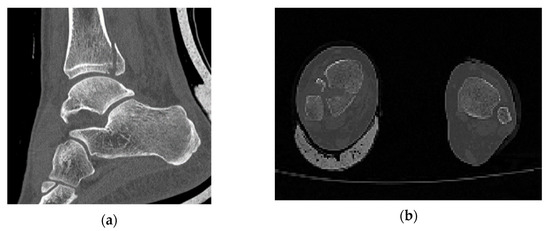

In comparison with industrial models, which are studied through computational methods, in biomechanics the object is not designed with a CAD software and its geometry varies randomly from person to person. In order to identify that the one and only fracture is the posterior malleolus fracture, all the ankle joint parts were thoroughly observed. The software RETOMO, as a tool, gave us the opportunity to run a 3D view around the CT scan and focus further on the fracture location. In practice, the tree dimensional image is recognized through the software and converted in a surface within the boundaries that the image defines. Afterwards, the surface is meshed and replaced with face elements. The first indication that the fracture is posterior malleolus, is given as when only the tibia has a broken part and the fibula appears complete (Figure 1). A second verification is that no fracture appears on medial malleolus.

Figure 1. (a) Section cut of the posterior malleolus fracture; (b) plan view (fracture shown on the left).